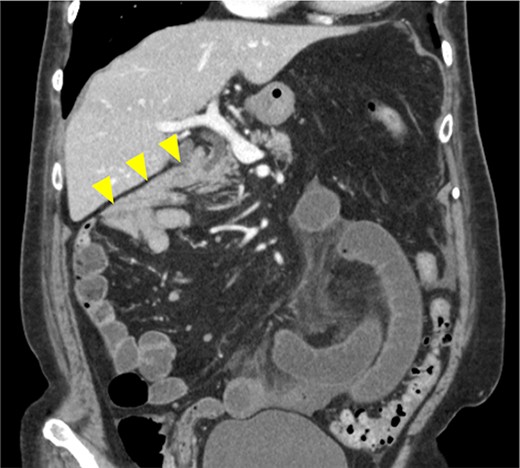

An 86-year-old woman with no prior abdominal surgeries was admitted to our hospital complaining of constant abdominal pain with an acute onset of 8 hr duration. The physical examination revealed tenderness of the lower abdomen. The laboratory test results were unremarkable, except for elevated lactate (3.0 mmol/l) and leukocyte counts (14 400/μl). Contrast-enhanced computed tomography (CT) revealed a closed-loop obstruction of the hypo-enhancing small bowel in the left lower abdominal quadrant, which suggested a strangulated bowel obstruction (Fig. 1). The duodenum did not form a horizontal limb and ran caudally to the jejunum (Fig. 2). The duodenojejunal flexure was abnormally located in the right upper abdominal quadrant, which suggested an intestinal malrotation. Sac-like capsulated small-bowel loops were barely visible.

Images from enhanced CT. (a) Arterial-phase axial CT shows a hypo-enhancing small bowel in the left lower abdominal quadrant. (b) Arterial-phase coronal CT coronal enhanced CT shows a closed-loop obstruction of the hypo-enhancing small bowel (arrow).

Image from enhanced CT. Contrast-enhanced CT shows the absence of a horizontal duodenal leg and the duodenum running caudally to the jejunum (arrowhead).